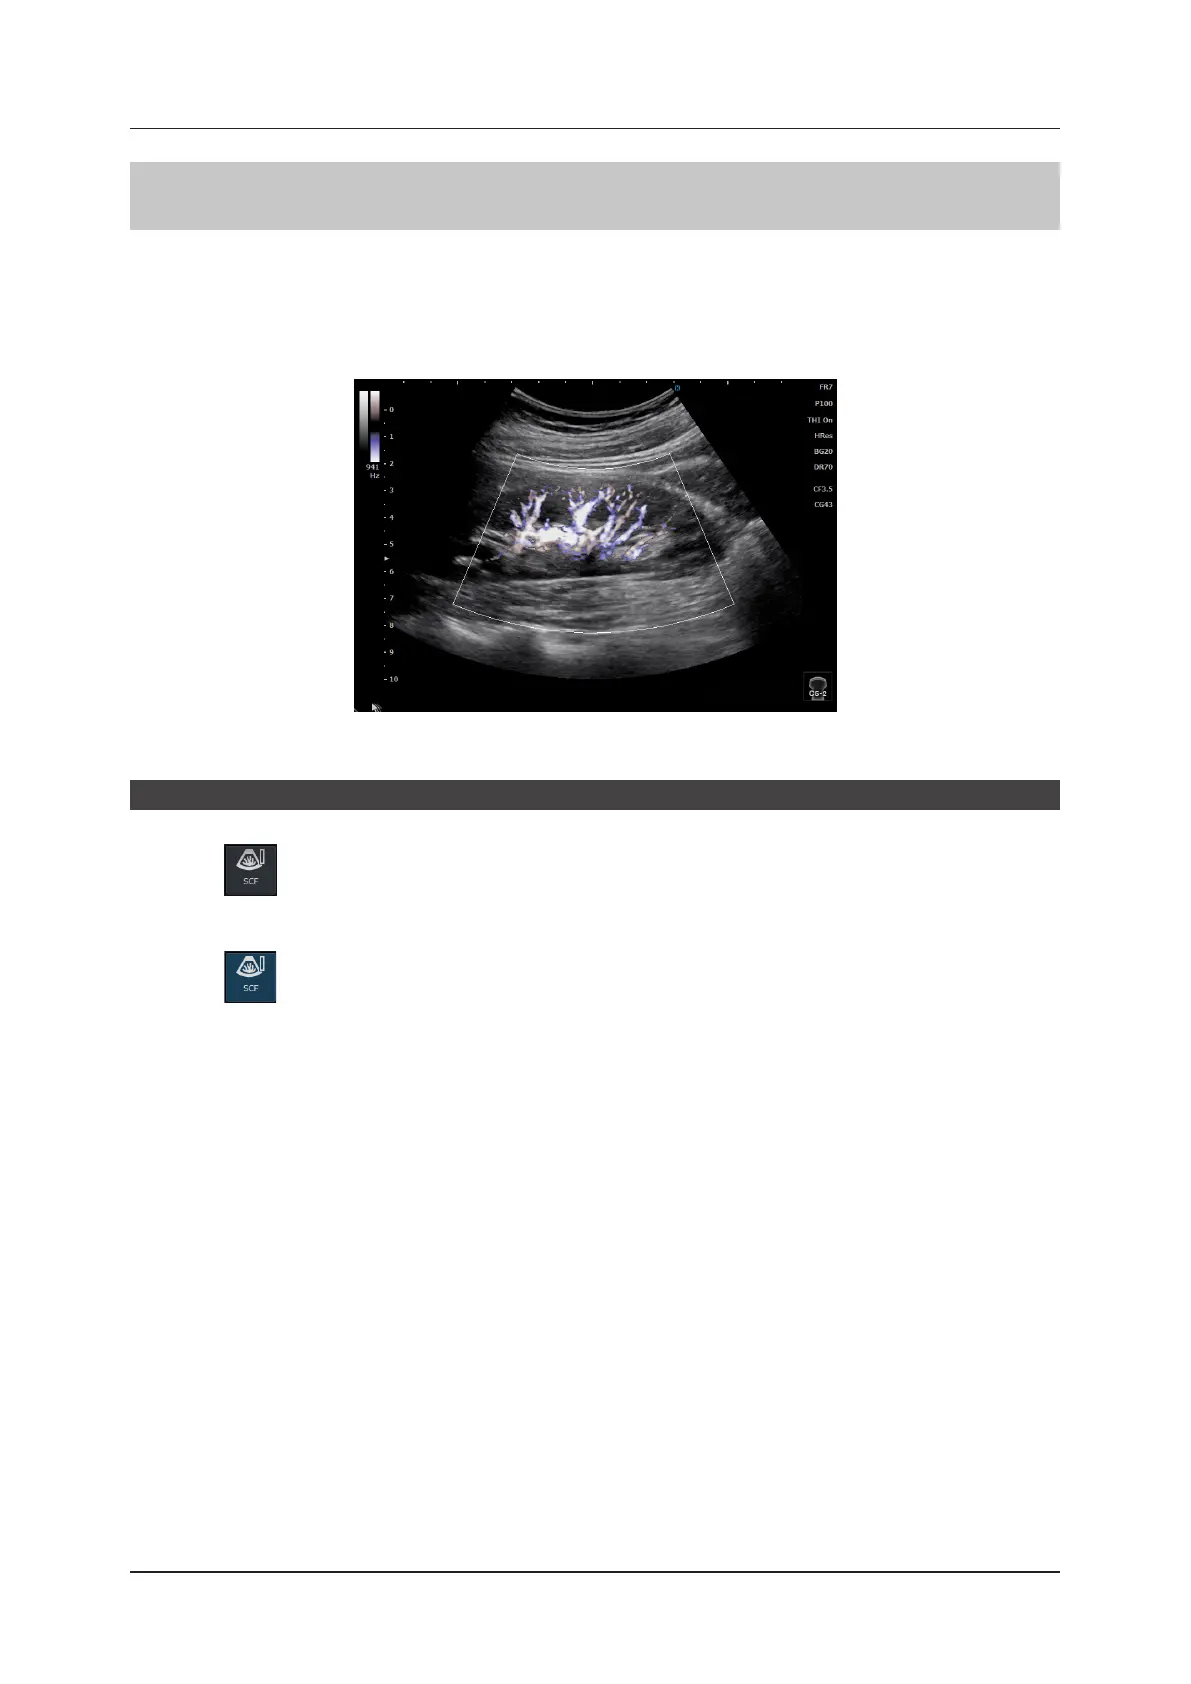

4.4.6 SCF-mode

In SCF-mode, color blood ow patterns are displayed within the Region of Interest (ROI) in a B image.

This mode is suitable for a study to display blood ow in a section close to the body surface with resolution higher

than that in the Color Flow-mode. This mode allows you to display a C ROI and adjust the size within a B image.

<SCF image>